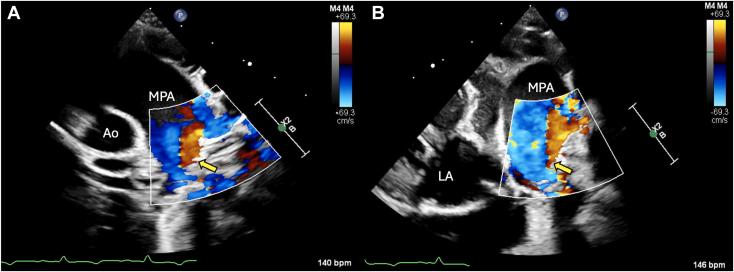

Multimodal Imaging Diagnosis of Doubly Committed Juxta-Arterial Ventricular Septal Defect and Persistent Left Cranial Vena Cava in a Goat.

CASE (Phila). 2024 Jun 4;8(7):395-400. doi: 10.1016/j.case.2024.05.004. eCollection 2024 Jul.

• Multimodal imaging contributes to understanding of caprine congenital heart disease. • Echocardiography is useful for identification of DCJA VSD. • 3D heart models aid in assessing vascular anomalies not noted on echocardiography.